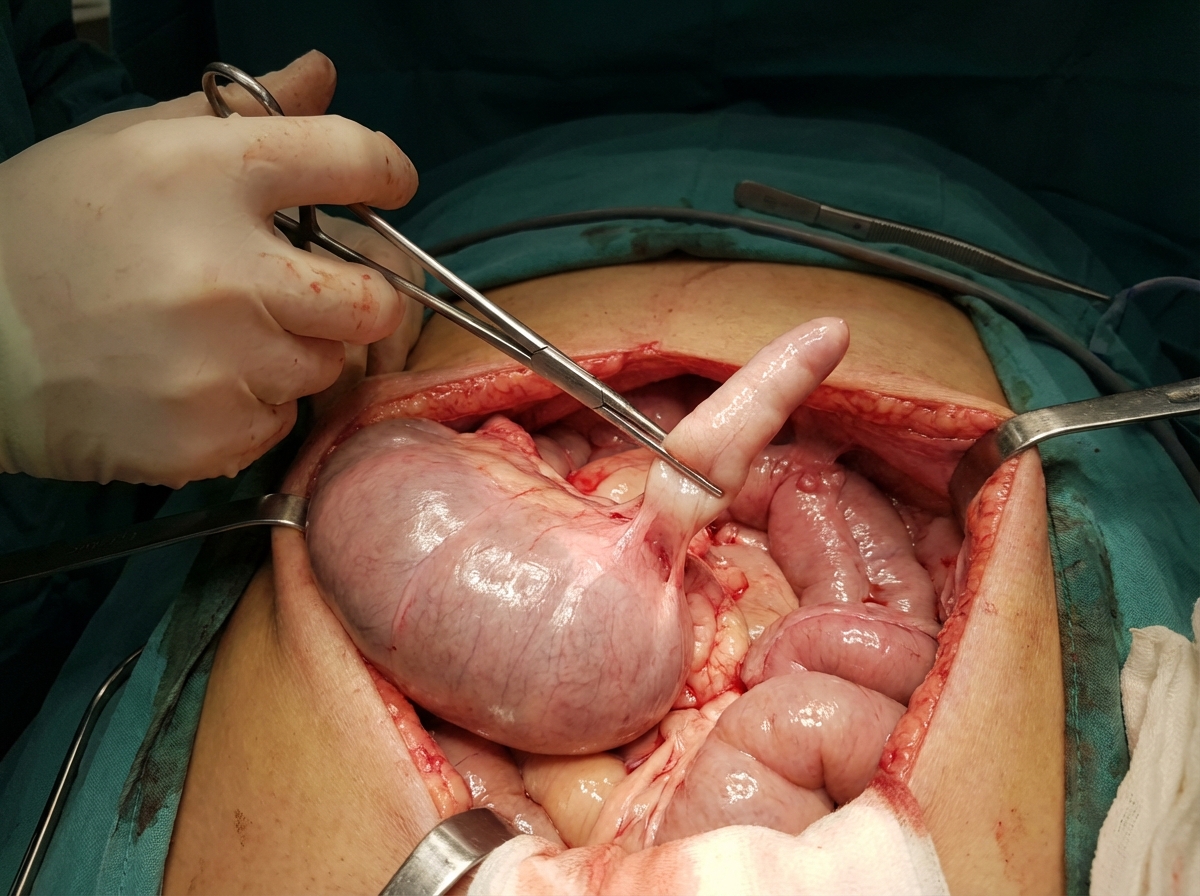

Identify the structure held with artery forceps:

Explanation: ***Appendix*** - The image shows a **vermiform appendix** — a small, finger-shaped organ projecting from the **large intestine** near the ileocecal junction. It is being held by artery forceps. - The characteristic blind-ended tubular structure attached to the cecum is clearly visible, consistent with the anatomical location and appearance of the appendix. *Meckel's diverticulum* - A Meckel's diverticulum is an **outpouching of the small intestine** (ileum), which would appear as an extension of the ileal wall, often with its own mesentery. - While it can be confused with the appendix, its origin from the small bowel and often broader base or different internal lining (gastric or pancreatic tissue) usually distinguishes it. *Zenker's diverticulum* - Zenker's diverticulum is an **outpouching of the pharyngeal mucosa** (a false diverticulum) located in the upper esophagus. - This structure is found in the **neck/mediastinum**, completely unrelated to the intra-abdominal organs shown in the image. *Colostomy stoma* - A colostomy stoma is a **surgically created opening** of the colon onto the surface of the abdomen, designed to divert fecal matter. - This image clearly depicts an **intra-abdominal organ** being manipulated during surgery, not an externalized stoma. *Fallopian tube* - The fallopian tube is a **paired tubular structure** in the female reproductive system extending from the uterus to the ovary. - While tubular, it has a different anatomical location (adnexa/pelvis) and arises from the uterus, not the cecum, with a more delicate, fimbriated distal end.